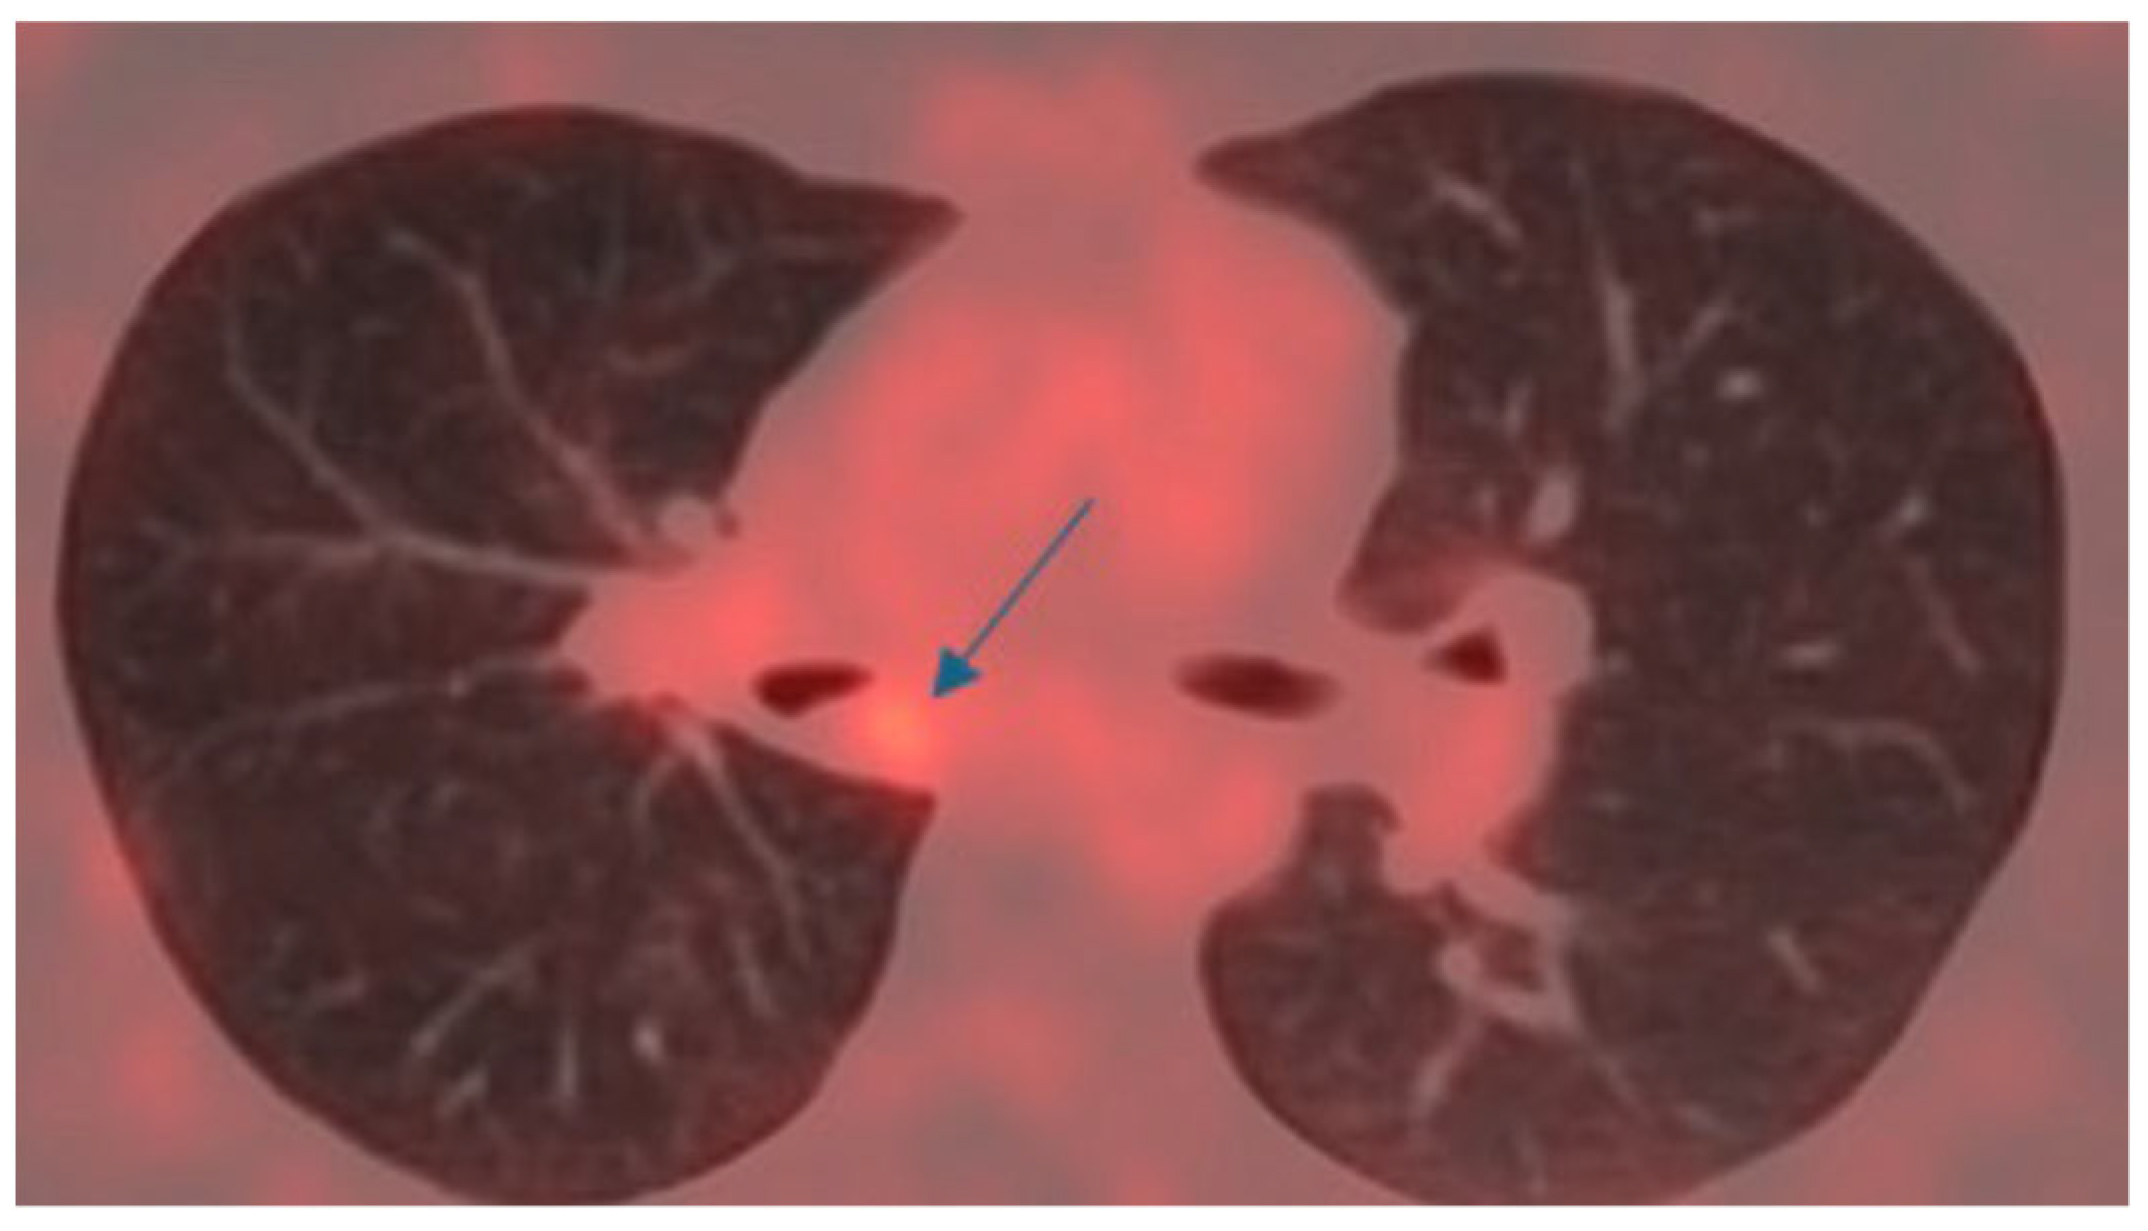

4.1. Case 1